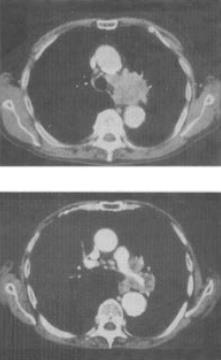

患者男,59岁,咳嗽,咳痰,痰中带血2个月余,CT检查如图,最可能的诊断是()。

A、肺结核

B、中央型肺癌

C、矽肺

D、肺炎

E、肺错构瘤

正确答案:

B